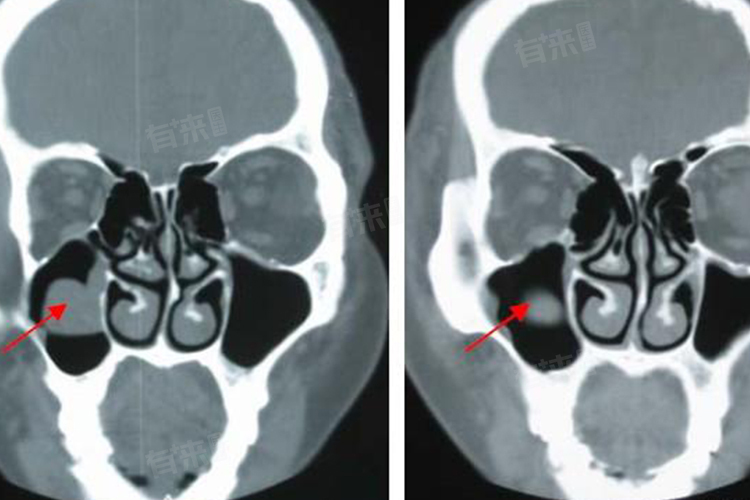

左侧上颌窦黏膜增厚是一种在鼻窦影像学检查,如鼻窦CT或X光中常见的表现,这意味着左侧上颌窦的黏膜出现了炎症反应,导致其厚度增加。

- 正常情况下,上颌窦黏膜是很薄的一层组织,可以分泌黏液,帮助湿润和过滤进入鼻腔的空气,还具有一定的免疫功能。当细菌、病毒等病原体入侵上颌窦,或者由于过敏等因素,就会引发炎症。在炎症状态下,上颌窦黏膜会出现充血、水肿,进而导致厚度增加。

- 左侧上颌窦黏膜增厚可能会伴随着一些症状,比如患者可能会出现鼻塞,这是因为上颌窦开口被增厚的黏膜部分堵塞,导致鼻窦内的空气流通不畅,还有可能出现流涕,由于炎症刺激黏膜分泌更多的黏液,而且因为鼻窦引流不畅,黏液就会从鼻腔流出。患者还可能会感觉到面部胀痛,尤其是在左侧面颊部位,这是因为上颌窦内压力增加,对周围的骨壁产生压力。不过也有一些患者可能没有明显的症状,只是在进行影像学检查时偶然发现上颌窦黏膜增厚。